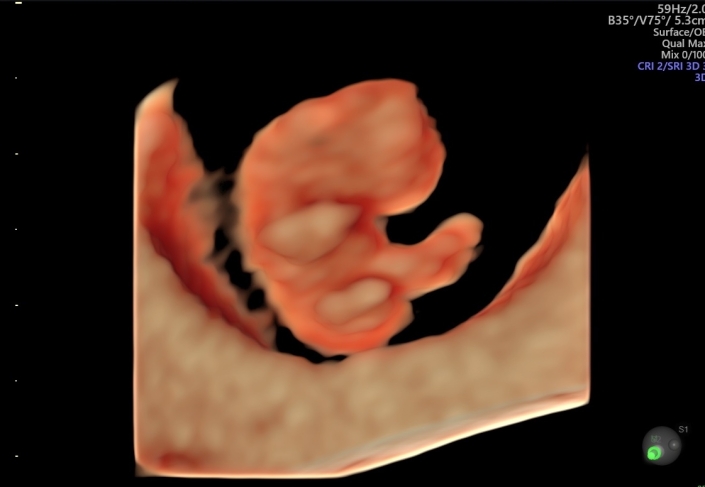

Das Angebot der erweiterten pränatalen Diagnostik in unserer Praxis erstreckt sich vom erweiterten Erst-Trimester-Screening mit Nackentransparenzmessung (lizenziert durch die FMF-London) und Hormondiagnostik (PAPP-A, f. ß-HCG), frühem Organultraschall und fetaler Echokardiographie, über die Feindiagnostik/Organultraschall im zweiten Trimester mit fetaler Echokardiographie und farbcodierter Doppleruntersuchungen bis hin zur invasiven Diagnostik mit Chorionzottenbiopsie (Mutterkuchenbiopsie) und Amniocentese (Fruchtwasserpunktion).

Mit dem Voluson E10 ® von GE steht uns ein modernes Hochleistungs-Ultraschallgerät zur Verfügung.

Das Voluson E10 ®, ein Produkt der GE-Expert-Serie, wurde speziell für die fortschrittliche und subtile Feindiagnostik in Gynäkologie und Pränatalmedizin entwickelt. Wo komplexe Fälle nicht die Ausnahme, sondern die Regel sind. Wo schwierige diagnostische Fragen tagtäglich zu lösen sind. Wo Patienten eine umfassende Information und Beratung erwarten.

Insgesamt sind im Rahmen der Mutterschutzrichtlinien drei Ultraschalluntersuchungen vorgesehen:

- von Beginn der 19. bis zum Ende der 22. Schwangerschaftswoche